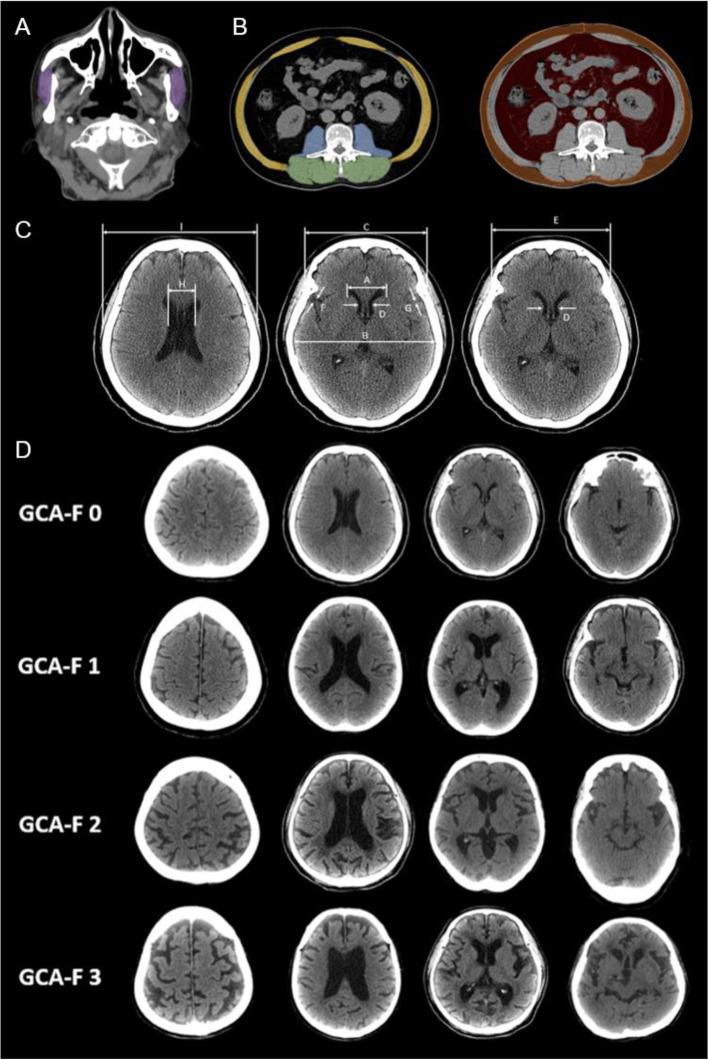

This cross-sectional study included 168 elderly patients who visited the multi-disciplinary dementia outpatient clinic at Kaohsiung Chang Gung Memorial Hospital for memory issues, between 2017 and 2019. The body composition was assessed by dual energy X-ray absorptiometry (DEXA) and CT based skeletal muscle index including L3 skeletal muscle index (L3SMI) and masseter muscle mass index (MSMI). The brain atrophy assessment was measured by CT based visual rating scale. Possible predictors of low lean mass in the elderly with cognitive impairement were identified by binary logistic regression. ROC curves were generated from binary logistic regression.

本横断面研究纳入了 2017 年至 2019 年间因记忆力问题到高雄长庚纪念医院多学科痴呆门诊就诊的 168 名老年患者。采用双能 X 射线吸收法(DEXA)和基于 CT 的骨骼肌指数(包括 L3 骨骼肌指数(L3SMI)和咬肌肌肉质量指数(MSMI))评估身体成分。采用 CT 基于视觉评分量表评估脑萎缩。通过二元逻辑回归确定认知障碍老年人低瘦体重的可能预测因素。从二元逻辑回归中生成 ROC 曲线。